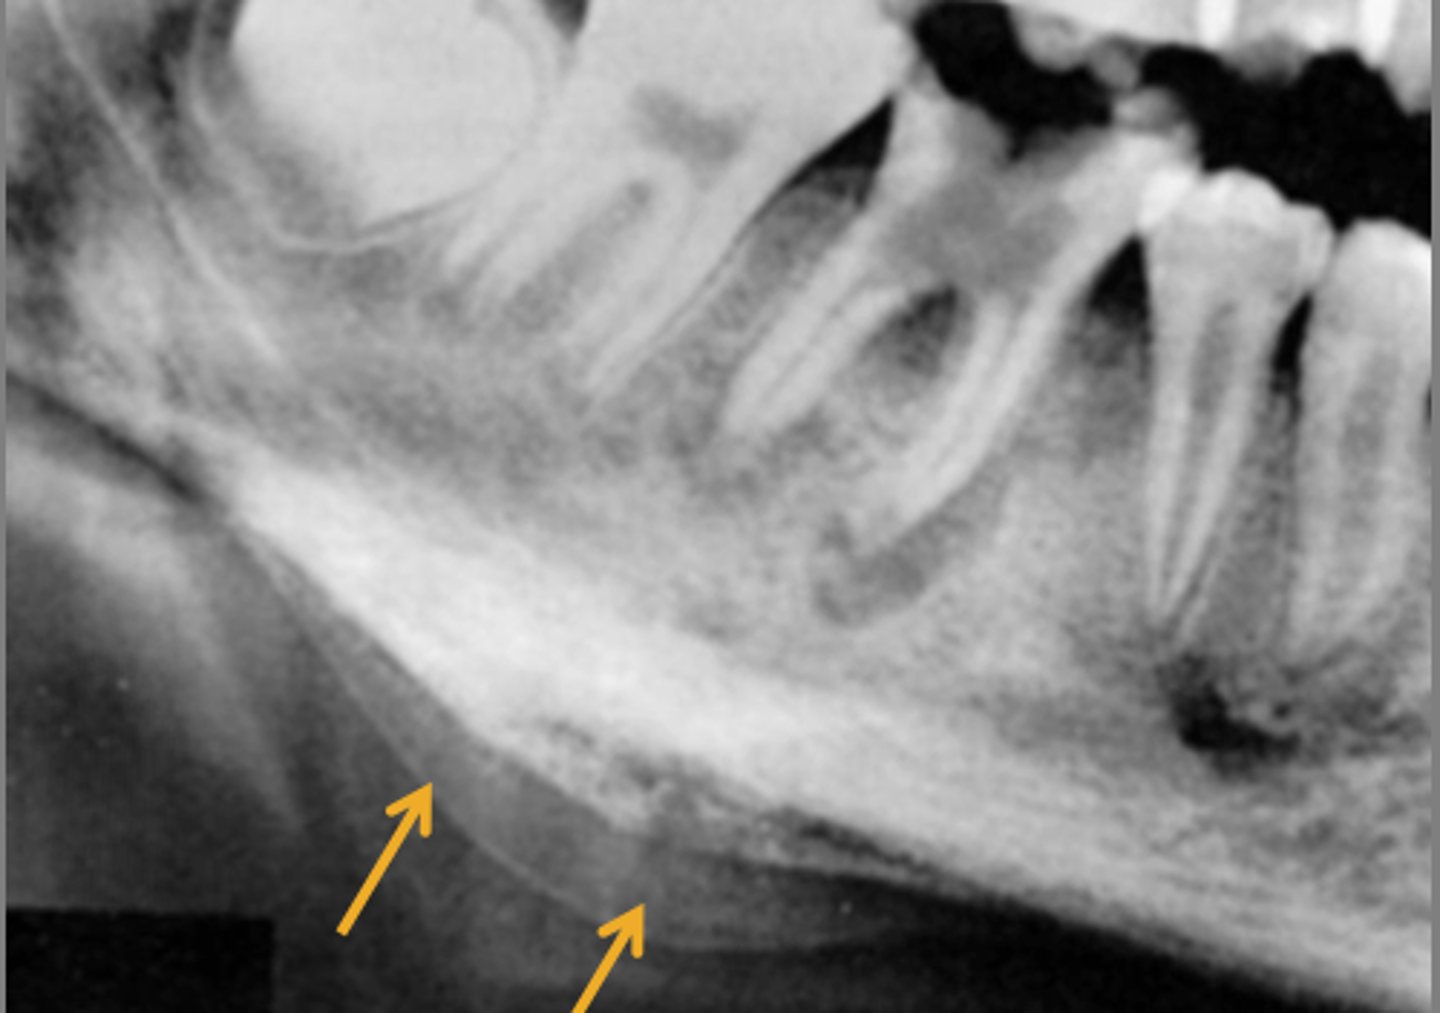

Proliferative Periostitis /Garre's Osteomyelitis

younger patient

female

rare nonsuppurative type

mild infection below periosteum

inferior border of the mandible

hard bony swelling

Radiographic Features of Proliferative Periostitis

thin convex shell of bone

laminated/onion skin appearance